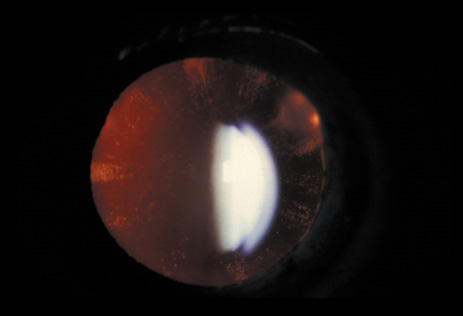

The dense bilateral lens opacities may present as a biconvex-shaped cataract or as posterior, polar, nuclear, or total cataract. The discoid lens shape may result from loss of lens material due to a posterior lens capsule defect4 or defective lens fiber formation and subsequent degeneration.5 The cataracts are present at birth, and glaucoma may be present congenitally or develop within the first 3 years of life. Other ocular findings may include corneal opacity, mitotic pupil, enophthalmos, and hypotonia.6 The cognitive impairment presents with a discrete behavioral phenotype that includes temper tantrums, irritability, complex repetitive behaviors, and unusual mannerisms. Severe renal Fanconi's syndrome may lead to progressive renal impairment. Most boys will develop a distinctive facies and habitus, and attain a height of less than 5 feet because of developmental retardation. Female carriers manifest characteristic but usually asymptomatic lenticular opacities that will correctly identify carrier status with 100% sensitivity in postpubertal females. These opacities are typically small, irregularly shaped, off-white or gray in color, nonrefractile in appearance, and distributed around the lens equator, more anteriorly than posteriorly (Figs. 1 and 2). Most importantly, and distinctively, these opacities are clustered in radial bands or wedges in the peripheral cortex of the lens and are visible by retroillumination. Typically, the opacities are moderately dense for one or two clock-hours, are then less numerous or even absent for another clock-hour or two, and so on. These opacities must be differentiated from the polychromatic, iridescent “crystals” found in Steinert's myotonic dystrophy (DM), gray-white random opacities in carriers of X-linked adrenoleukodystrophy, sutural opacities in Nance-Horan's (NH) syndrome, snowflake granules beneath the anterior and posterior capsule in diabetes mellitus, highly uniform white dots of hypoparathyroidism, and equatorial opacities in cataracta coronaria or ceruleana. Some females also manifest a dense white, central, posterior cortical cataract in the precapsular area. Although the posterior central cataract is apparently congenital, the equatorial and anterior cortical punctate opacities are uncommon in prepubertal female Lowe's syndrome carriers.7 Carrier status may also be confirmed by DNA diagnosis.

Fig. 1. OCRL. Female carrier with typical small, irregularly shaped, off-white or gray, nonrefractile opacities in the anterior lens cortex, slit-lamp view. (Courtesy of Dr. R.A. Lewis, Baylor College, Houston, Texas.)